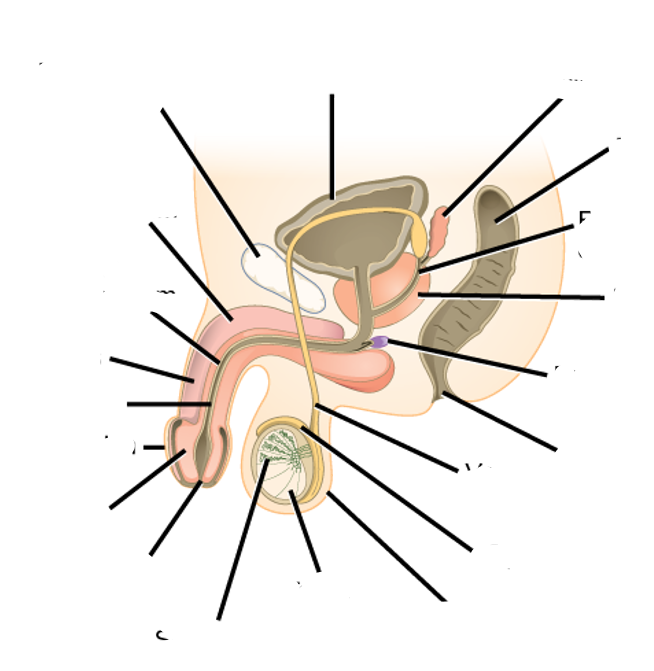

what does this image show